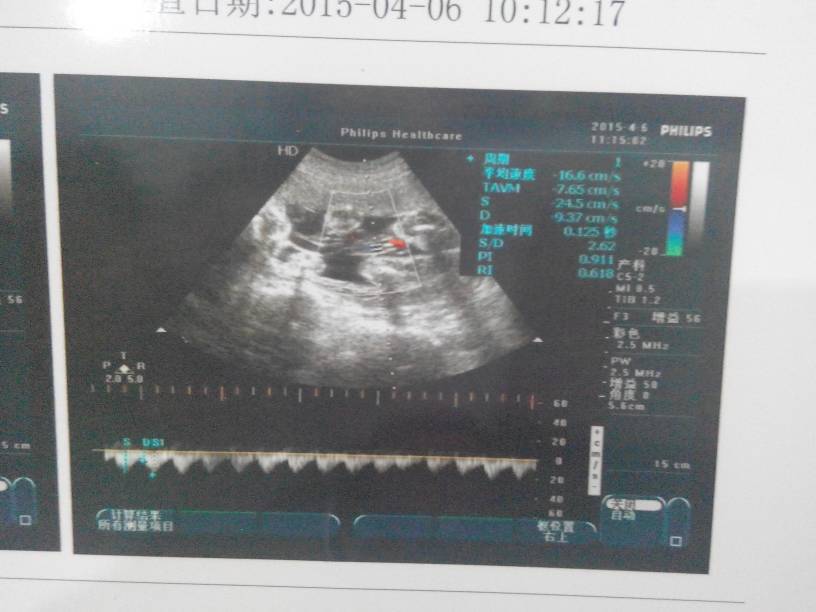

求大神解答,我这孩子是男是女,我不男女,我给我孩子准备衣服,谢谢啦 求大神解答,我这孩子是男是女,我不男女,我给我孩子准备衣服,谢谢啦 点击展开 小脸萌哒哒 2015-04-18 13:25 为您推荐: 其他回答 看不出来的 卿卿我心 2015-04-18 13:47 那你就多花点钱去做B超会说的他们! 152*****158_UobO 2015-04-18 13:39 小孩子的衣服都是白色和粉色的比较多 簡箪暧 2015-04-18 13:36 这个看不出来的……… 小熊朵朵 2015-04-18 13:35 买浅颜色的衣服,男女都可以穿。 伶仃飞吴 2015-04-18 13:33 加载更多 相关问题 亲们帮我看看这是男是女啊,男女都好,我只是想提前准备宝宝衣服 0-7岁的小孩每个年龄阶段应该穿多大的衣服?还有哪些要注意的呢?拜托各位大神 怀孕第几个月可以开始准备BB的衣服了?谢谢了,大神帮忙啊